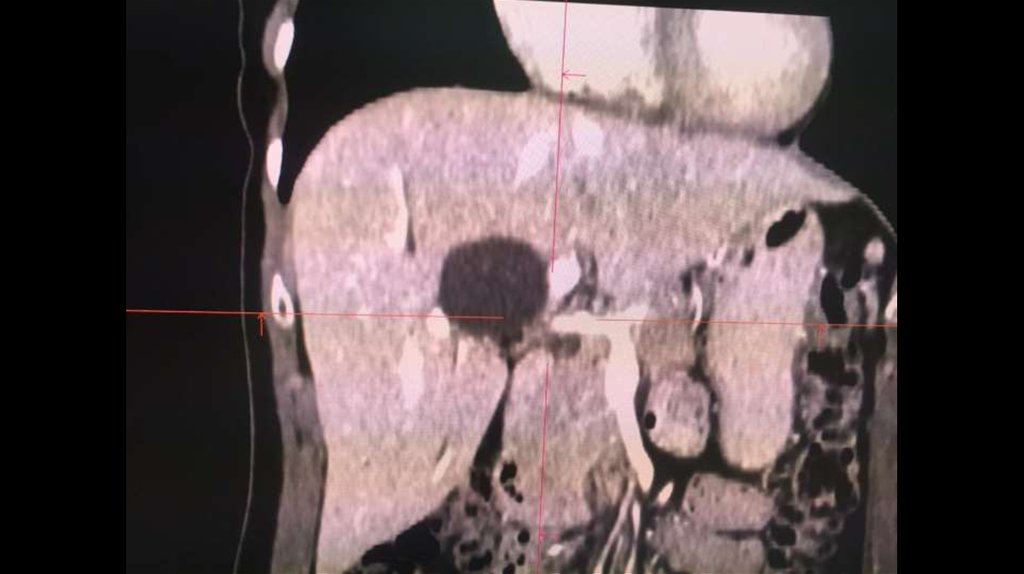

По направлению из ЦГБ в ККБ №1 поступил пациент М., 48 лет, с диагнозом «Эхинококкоз

печени»

Пациенту в плановом порядке выполнено КТ ОБП. По результатам исследования выявлена

эхинококковая киста IV-V сегментов.